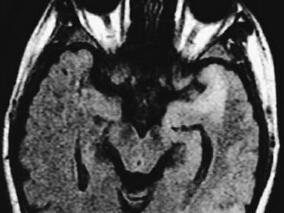

1小时条评论女,36岁,未婚。 主诉:抽搐1年,精神异常2个月。 病史:患者近1年内或无明显诱因或在情绪激动后出现四肢抽搐,双上肢屈曲,双下肢伸直,头颈前屈,伴意识丧失、口吐白沫,符合强直-阵挛发作表现,无二便失禁和舌咬伤,每次发作约3~4分钟,均于白天出现,前后共...